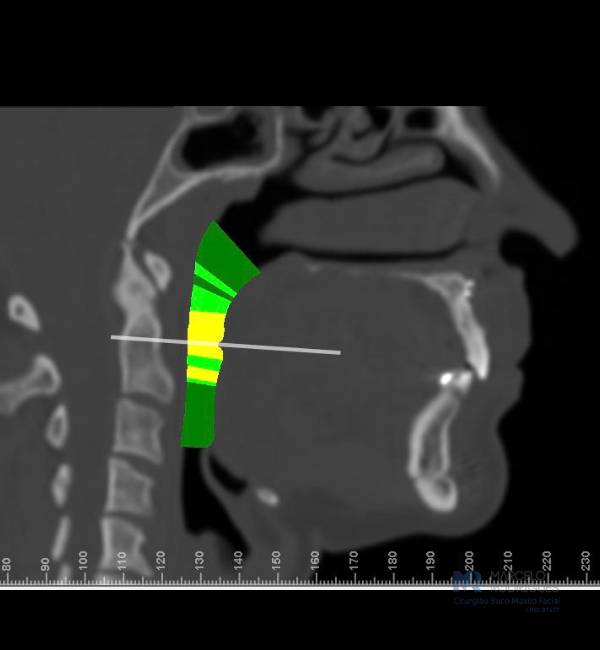

A síndrome da apneia obstrutiva do sono é uma condição na qual ocorrem problemas significativos de obstrução das vias aéreas durante o sono. A causa mais comum dessas obstruções envolve obstrução nasal e/ou diminuição do espaço das vias aéreas orofaríngeas (espaço entre a parte posterior da língua e a parte posterior da garganta).

Existem tratamentos clínicos com uso de aparelhos chamados CPAP, tratamentos odontológicos com uso de aparelhos intra-orais, e quando necessário, tratamentos cirúrgicos mais complexos.